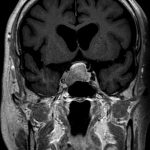

断層撮影

手術前1